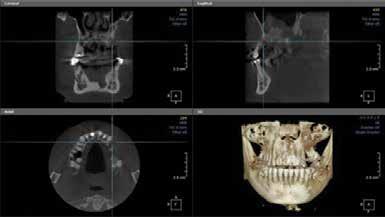

Proton density (left) and CBCT (right) images of apical lesion and furcation involvement at tooth #2. This tooth was clinically diagnosed with pulpal necrosis and a crack involving the furcation.

Proton density image showing improved image detail provided by dental dedicated MRI coil.